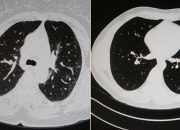

Covid’e yakalanan 2 gencin tomografisi Elazığ’da Göğüs Hastalıkları Uzmanı Dr. Cebrail Azar, geçtiğimiz yıla oranla yoğun...